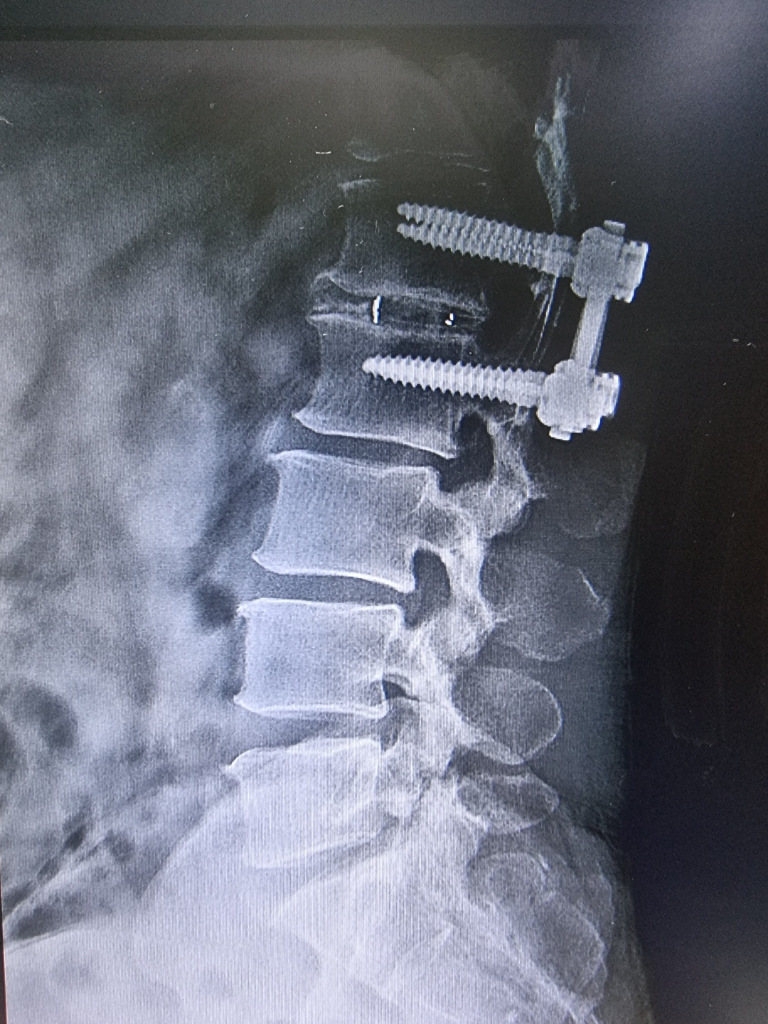

디스크가 약간 튀어나와있긴 하지만 비가역적인 변화가 생기지는 않은것으로 판단됩니다.

디스크의 정식 병명은 추간판 탈출증으로 추간판의 수핵이 탈출하여 신경을 압박함으로서 나타나는 일련의 증상입니다. 추간판 탈출증의 경우 시간이 지나면서 돌출된 수핵은 면역기전에 의해 저절로 줄어들어 증상이 완화되는 경우도 있습니다. 하지만 신경학적 이상이 동반되거나 경우에 따라 빠른 감압술이나 수술이 필요할 수도 있으므로 주치의와 상의하시는 것이 좋겠습니다.